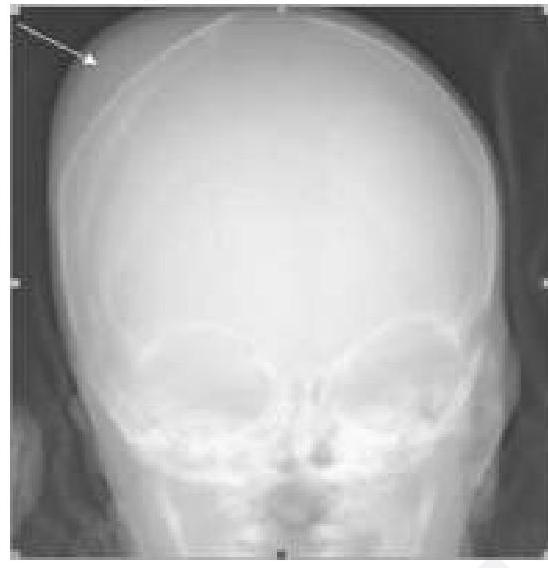

Identify the instrument shown in the image.

Explanation: ***Ureteroscope*** - The image distinctly shows a long, thin, flexible scope with a working channel, consistent with a **flexible ureteroscope**. - The presence of a **guidewire** alongside the scope further indicates its use for navigating the narrow and tortuous ureter. *Nephroscope* - A nephroscope is typically a more rigid and wider instrument used for percutaneous access to the **kidney's collecting system**. - Its design is optimized for procedures within the kidney, not for navigating the ureter. *Cystoscope* - A cystoscope is used to visualize the **bladder** and urethra and is generally shorter and thicker than a ureteroscope. - While it can be flexible or rigid, the instrument shown is too long and thin to be a standard cystoscope. *Laparoscope* - A laparoscope is a rigid instrument used for **abdominal surgery**, inserted through the abdominal wall. - Its design and application are entirely different from the instrument shown, which is designed for internal urinary tract procedures.